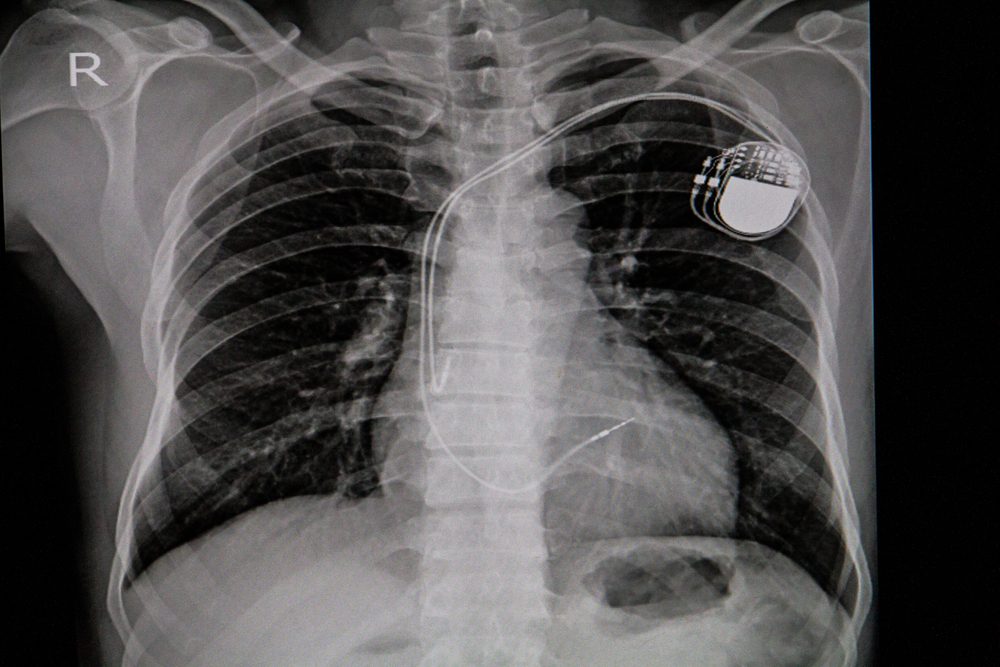

Chest x-ray image of permanent pacemaker implant in body chest.

Richman Photo/Shutterstock

Sign: You already have heart problems

If you already have a heart condition, any rhythm problems can be more serious. “A person with a weakened heart, or cardiomyopathy, may also be predisposed to have extra ventricular beats [from the bottom chambers of the heart],” explains Dr. Lau. “When these heartbeats become frequent and fast, they are termed ‘ventricular tachycardia, and in a weakened heart that may lead to cardiac arrest.”